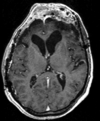

Within Exam:

Exam 1 DWI aligned to T1